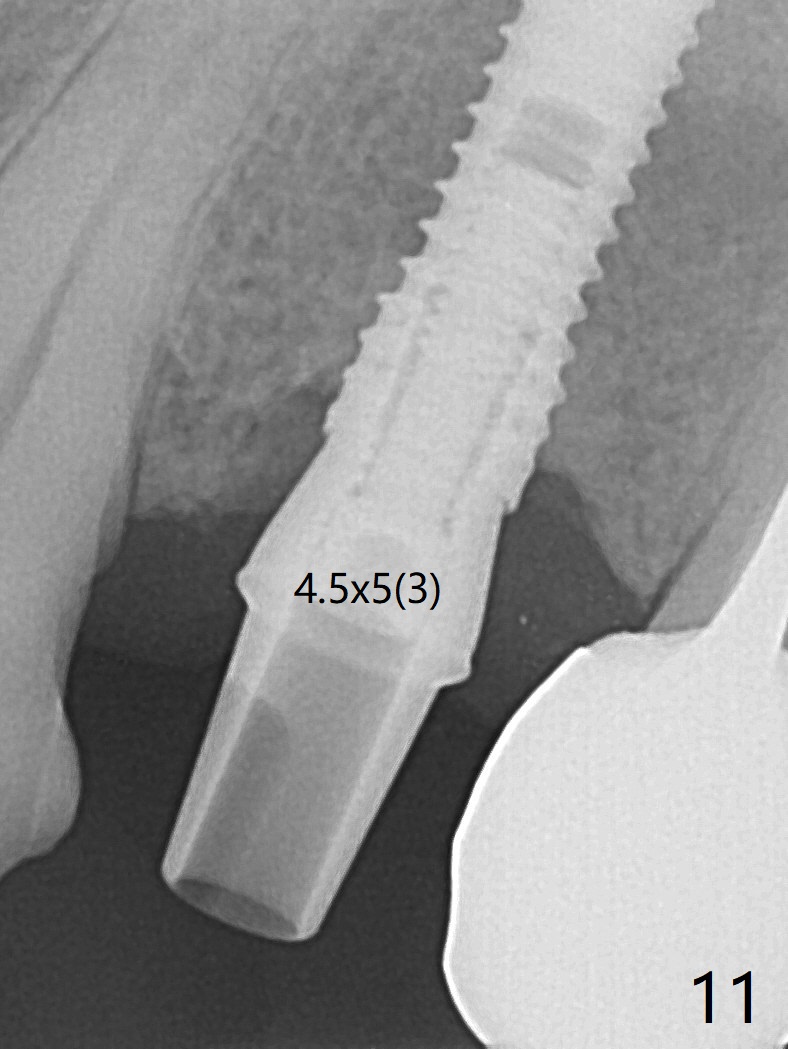

After extraction of the oval-shaped residual roots at #12 (Fig.1), osteotomy is initiated in the palatal socket for 18 mm; since the root of the canine curves distal (Fig.2 red dashed line), the osteotomy cannot afford to move mesial and extend more apical. A 3.8x15 mm implant is placed with > 50 Ncm (Fig.3). With immediate placement of a 4.5x4(3) mm abutment, an immediate provisional is fabricated to close the sockets (Fig.4 P). The provisional has clearance from the RPD clasps (Fig.5). In fact the implant could be longer, as shown by immediately postop panoramic X-ray (Fig.6). The implant seems to be osteointegrated 3 months postop (Fig.7). The tooth #13 is symptomatic with caries (Fig.8 C) 7 months post #12 crown cementation; the #13-15 FPD dislodges. The upper left quadrant is cold and hot sensitive 2.5 months post RCT (Fig.9); although there is mild percussion at #13, pulpal test shows that the tooth #15 has lingering pain. The FPD was recemented temporarily after RCT; it cannot be removed. The implant crown has been loose for several months during the pandemic before he returns 2 years 7 months post cementation. In fact the abutment has been not seated completely (from Fig.3 to 9). The crown/abutment is removed from the mouth; the crown is sectioned and separated from the abutment; the latter is reseated, but incompletely (Fig.10 <). With suspicion of the mesial crestal contact, profile drills 4.6 and 5.5 mm are used without effect. A new (old probably being worn) and longer (easy to turn in the narrow space) abutment is finally seated completely (Fig.11 (no gap)). After occlusal adjustment, abutment level impression is taken for a new crown.